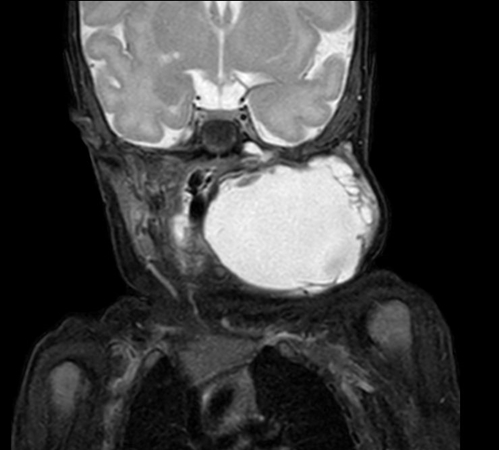

Coronal mDIXON XD - T2w TSE (Water only)

Coronal mDIXON XD - T2w TSE (In Phase)